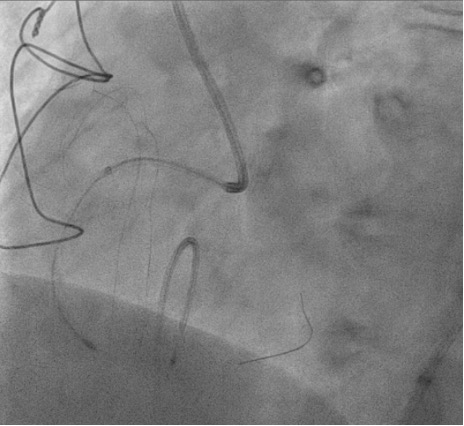

Right femoral arterial access was taken with 7F long sheath (45cm) and RCA was engaged with 7F AL 3.5 catheter. We failed to cross proximal lesion with Rinato wire (Asahi Intecc, Japan) but crossed with Fielder XT-R (Asahi Intecc, Japan). We had difficulty in crossing the distal lesion due to inadequate guide support and inability to deliver microcatheter beyond proximal calcific lesion. Proximal lesion was predilated with 2.5 mm NC balloon but the balloon got ruptured. Fielder XTR wire was exchanged with Rota floppy wire (Boston scientific, Japan) with corsair microcatheter (Asahi Intecc, Japan) delivered just beyond proximal lesion. Temporary pacemaker inserted and Rotablation of the proximal RCA lesion was done with 1.5 mm Rota burr. Post proximal lesion modification corsair could be delivered to Distal lesion, and lesion crossed with Ultimate Bros 3 (Asahi Intecc, Japan) followed by de-escalation to Fielder XT-R wire. The proximal lesion was then dilated with 3.5x10mm Wolverine Cutting balloon (Boston Scientific, Ireland) to deliver a 7F Guideliner beyond the proximal lesion for better support to further gear advancement. As 1mm balloon stuck within the distal lesion, grenadoplasty was performed followed by an exchange to rota wire with corsair. Rotablation of distal RCA lesion was done with 1.5 mm burr through guide extension. Further dilatation of distal lesion was done with 3mm IVL balloon followed by stenting with 3.25 x 28 mm drug-eluting stent with good TIMI 111 flow.